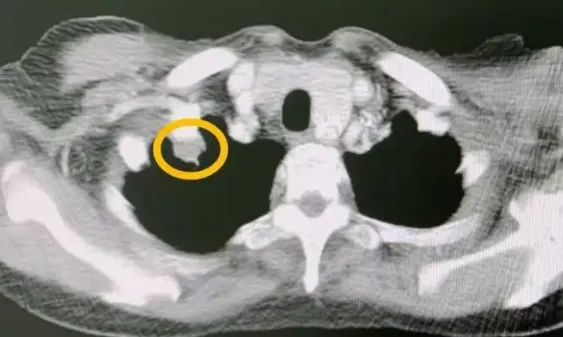

通过CT、MRI或PET-CT检查,如果发现原有肿瘤体积缩小30%以上,或者连续两次复查肿瘤没有增大、没有新发病灶,这在医学上被称为“部分缓解”或“疾病稳定”。